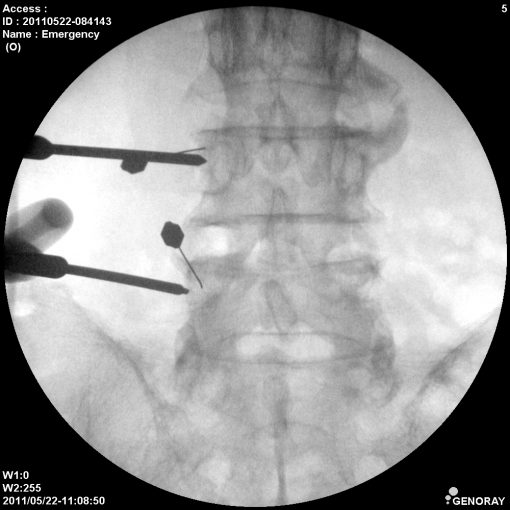

Аппарат применяется в различных областях медицины, таких как хирургия, ортопедия, педиатрия, травматология, урология и многих других. «АРХМ-РЕНЕКС» имеет широкий диапазон перемещений, легко позиционируется во всех направлениях, а так же имеет не большие габариты и вес обеспечивающие маневренность и простоту перемещений.

В качестве приемника используется усилитель рентгеновского изображения (УРИ) с ПЗС-матрицей 1024х1024 пикселей. Мощность рентгеновского питающего устройства 2,2 кВт.

- Непрерывная и импульсная рентгеноскопия с цифровой обработкой изображения.

- Цифровая рентгенография.